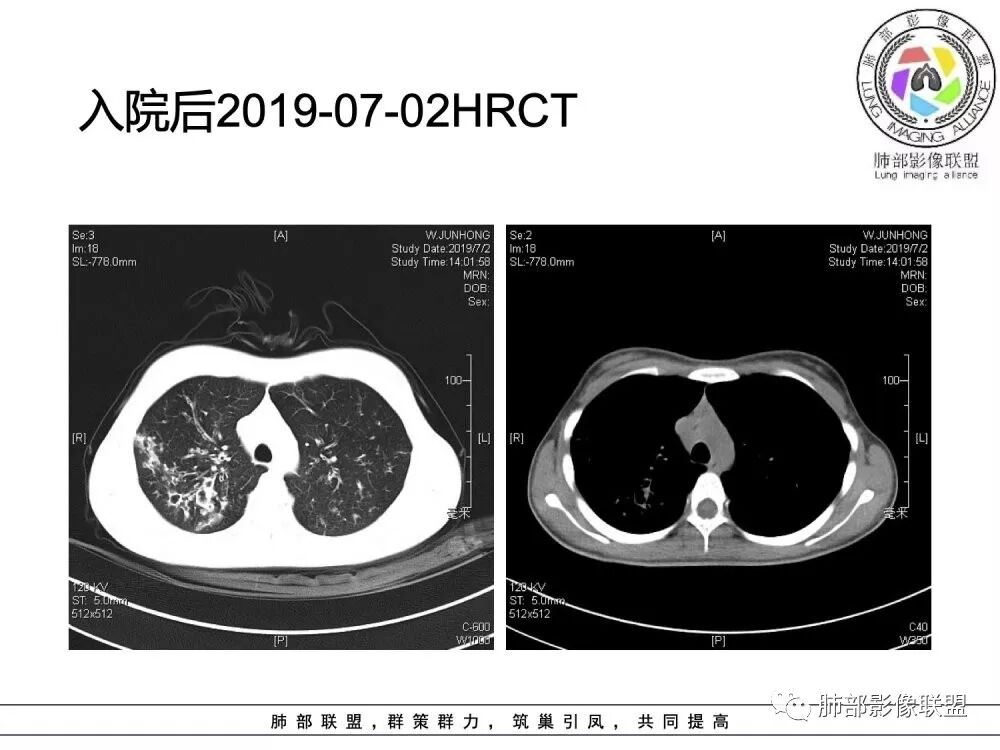

患者青少年女性,以反复咳嗽、咳痰10余年,痰血3年,再发1月余。患者自幼咳嗽、咳痰史,黄白脓痰,曾诊断支气管扩张症,常感乏力,时有腹痛感。有食物药物过敏史。胸CT:病变以双上肺为主,支气管明显扩张,支气管壁可见增厚,可见双轨征,右上肺后段可见囊状改变,并可见片状实变影。诊断考虑:囊性纤维化?鉴别:1 ABPA?2 结核后支气管扩张?

年轻女性,15岁,自幼咳嗽咳痰10余年,痰血三年。两肺呈支扩改变伴小片渗出,双肺上叶为主 。左下见指套状密度偏高影考虑粘液栓,右上部分局限性实变,从病史基本推出诊断,考虑CF。

水晶石头:

病变以双上肺为主,支气管明显扩张,支气管壁可见增厚,可见双轨征 右上肺后段可见囊状改变,并可见片状实变影。患者青少年女性,以反复咳嗽 咳痰10余年,痰血3年,患者自幼咳嗽 咳痰史,黄白脓痰,曾诊断支气管扩张症,考虑:囊性纤维化?

患者15岁,女性,反复咳嗽、咳痰10余年,痰血3年,再发1月余。有腹痛、食物药物过敏史。胸CT:病变双上肺为主,支气管明显扩张,支气管壁可见增厚,双轨征 ,部分可见囊状改变及片状实变影。诊断考虑:CF?鉴别:ABPA;纤毛运动障碍综合征;DBP等

(1)支气管壁增厚、支气管扩张

可广泛分布于两肺各叶,尤其是两肺上叶多见。支气管扩张主要是轻、中度柱状支气管扩张。支气管壁增厚既可发生于扩张的支气管,也可发生于非扩张的支气管,常为轻度增厚,管壁内外比较光滑。

(5)斑片状阴影

表现为感染性支气管肺炎和亚段肺不张。呈1~3cm大小不等的斑片状高密度影,上肺野常见或上肺野病灶分布较多。